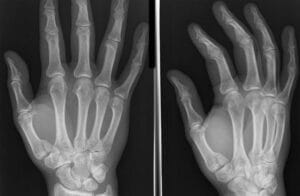

Figure1:

- X-ray Hand/Thumb (PA/Lateral/Oblique views)(Figure 1)

Based on fracture pattern (Figure 2)

- Extra-articular (Figure 1a and b)

- Oblique

- Transverse

- Intra-articular

- Bennett (Figure 1c and d)

- Rolando (Figure 1e)

- Comminuted